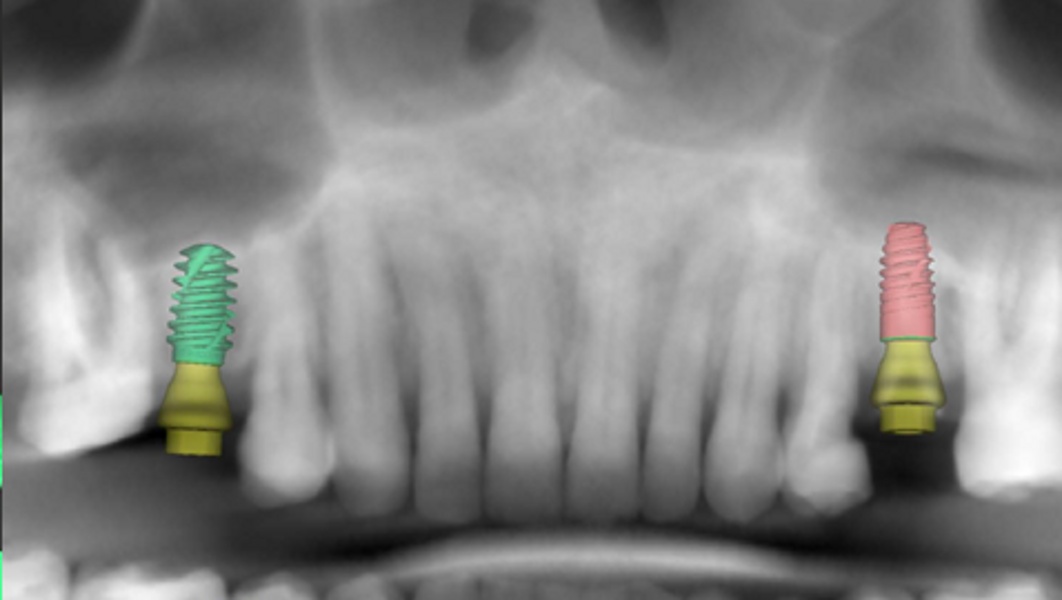

The patient’s maxillary and mandibular arches were scanned using the Straumann SIRIOS system. The scans, along with the DICOM files from the CBCT scan, were sent via Straumann AXS to Smile in a Box (Straumann) for treatment planning, surgical guide design and 3D printing of the model and surgical guides (Figs. 4, 5a–f & Figs. 6a–d).

After evaluation and validation of the plan, it was decided for site #15—where a residual root was present and the bone density was generally soft—that a Straumann BLX (Roxolid, SLActive, regular base) 4.5 × 8.0 mm implant would be placed, along with an M shape Straumann Anatomic Healing Abutment XC (regular base/wide base; gingival height: 1.5 mm). For site #25, extraction of the remaining root was planned and would be followed by the placement of a Straumann BLC (Roxolid, SLActive, regular base) 3.75 × 8.00 mm implant. This narrower site had a visible lamina dura, favourable for achieving primary stability. An M shape Straumann Anatomic Healing Abutment XC (regular base/wide base; gingival height: 1.5 mm) was also selected for this site to support proper soft-tissue emergence during the 60- to 90-day healing period. Owing to the expected post-extraction gaps between the implants and buccal bone walls, cerabone plus (botiss biomaterials) was planned to be used for grafting.